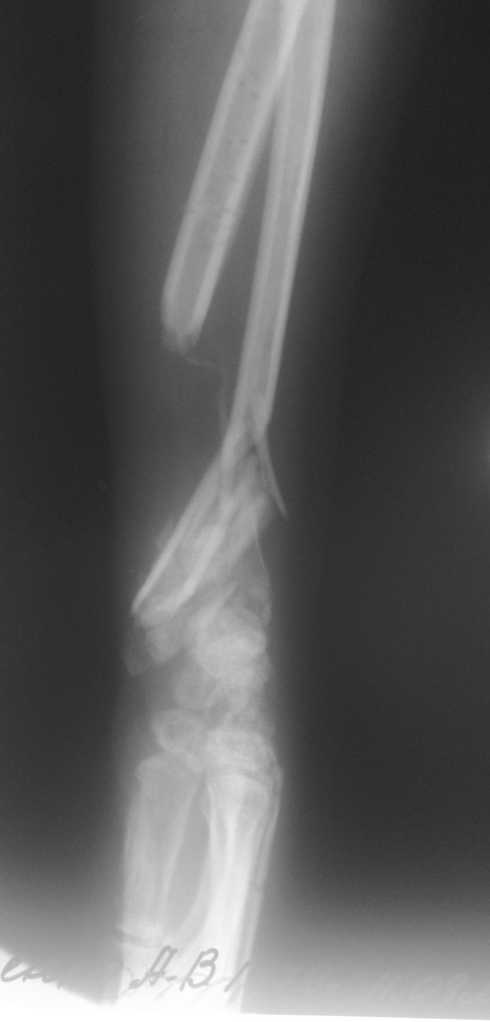

Имеется постттравматический дефект дистальных отделов костей левого предплечья.

Больная Д. 30 лет плучила травму 12.07.09г, пассажир скутера - тяжелая сочетанная травма брюшной полости и конечностей, гемоперитониум, закрытый перелом н\3 ЛЕВОГО БЕДРА, открытый перелом н/3 левого предплечья с дефектом обеих костей, рана голени. С момента травмы перелом предплечья был фиксирован анкерно-спицевым апаратом, проводилось лечение других сегментов. В настоящий момент АВФ демонтирован, имеется следующая рентгенологическая картина (см. приложение), имеется дефект обеих костей и суставных поверхностей. Коллеги подскажите варианты лечения в данном случае ?!